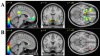

Objective: Consuming alcohol prior to a meal (an apéritif) increases food consumption. This greater food consumption may result from increased activity in brain regions that mediate reward and regulate feeding behavior. Using functional magnetic resonance imaging, we evaluated the blood oxygenation level dependent (BOLD) response to the food aromas of either roast beef or Italian meat sauce following pharmacokinetically controlled intravenous infusion of alcohol.

Results: BOLD activation to food relative to non-food odors in the hypothalamic area was increased during alcohol pre-load when compared to saline. Food consumption was significantly greater, and levels of ghrelin were reduced, following alcohol.

Conclusions: An alcohol pre-load increased food consumption and potentiated differences between food and non-food BOLD responses in the region of the hypothalamus. The hypothalamus may mediate the interplay of alcohol and responses to food cues, thus playing a role in the apéritif phenomenon.